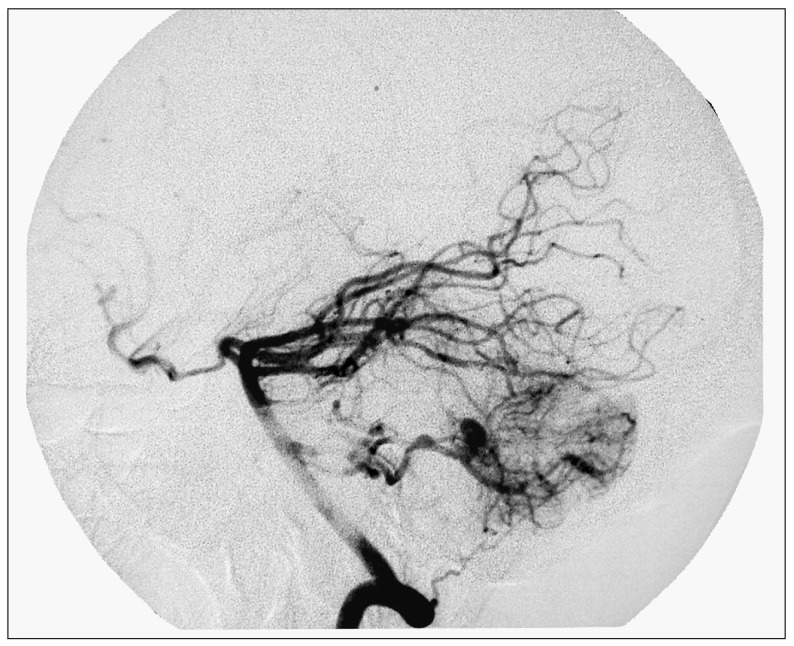

Figure 1.

male 32 years-old, cerebral hemorrhage in posterior fossa. DSA shows a nidus of AVM with an aneurysm beside the nidus feeding inferior posterior cerebellum artery.

Figure 2.

Superselective injection shows the nidus and the aneurysm clearly.

Figure 3.

The callback DSA shows that the nidus and the aneurysm have been eliminated completely after the injection of 2:1 NBCA through a Prowerl-14 microcatheter.